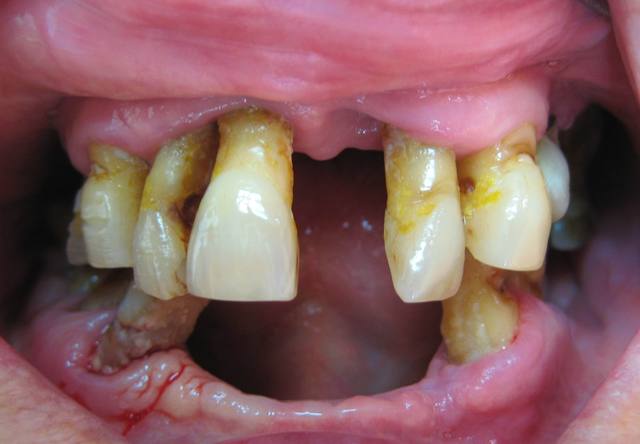

ça c'est un festival

c'est grave docteur ?

le haut a été fait soi disant il y à 2 ans

ça c'est du plan de traitement.